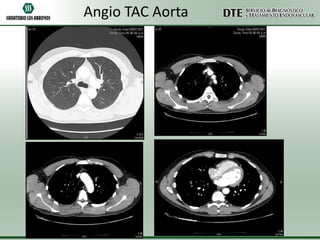

Angio TAC Aorta

abdominal y torácica

• Aorta torácica de diámetros conservados, en sus distintos trayectos.

•La emergencia de los vasos supraaórticos es de configuración y calibre conservado.

•Aorta abdominal de diámetros conservados, solo muestra placas de ateroma a nivel

infrarenal, sobre el sector latero-posterior izquierdo.

•Se menciona el nacimiento común de la arteria del T celíaco y la A mesentérica

superior.

•Las arterias renales muestran diámetros conservados.

•Las iliacas primitivas, internas y externas son de calibre conservado.

•Alteración de la morfología de múltiples arcos costales izquierdos. A cotejar con

antecedentes traumáticos.

•Quiste simple en el domo hepático.

•Resto sin particularidades.

Angio TAC Aorta •Aorta torácica de diámetros conservados, en sus distintos trayectos. •La emergencia de los vasos supraaórticos es de configuración y calibre conservado. •Aorta abdominal de diámetros conservados, solo muestra placas de ateroma a nivel infrarenal, sobre el sector latero-posterior izquierdo. •Se menciona el nacimiento común de la arteria del T celíaco y la A mesentérica superior. •Las arterias renales muestran diámetros conservados. •Las iliacas primitivas, internas y externas son de calibre conservado. •Alteración de la morfología de múltiples arcos costales izquierdos. A cotejar con antecedentes traumáticos. •Quiste simple en el domo hepático. •Resto sin particularidades.